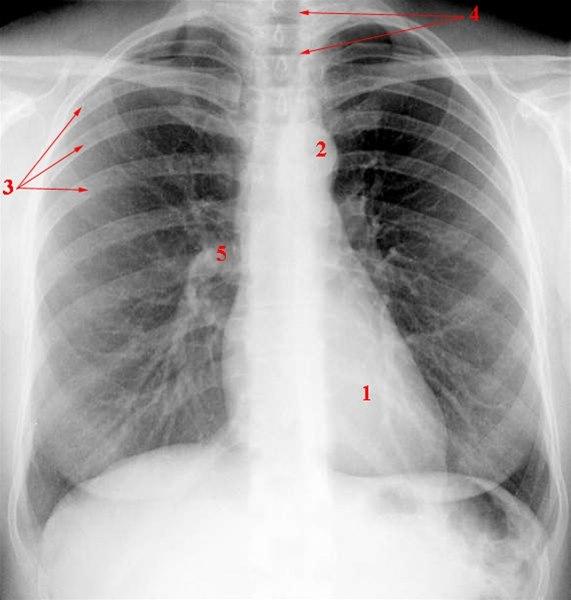

Etter inngrepet må du overvåkes som etter en torakotomi (åpning av brystkassen). Det må foreligge røntgenbilde 12 timer etter inngrepet for å avkrefte sammenfall av lungen (pneumotoraks).

Noen ganger er det nødvendig med ytterligere undersøkelser for å avklare problemstillingen. Det er oftest biopsier fra pleura, lunge, perikard, spiserør; eller bakteriologiske prøver fra pleuravæske, puss og perikardveske; eventuelt CT, MR eller røntgenbilder av brystkassen.